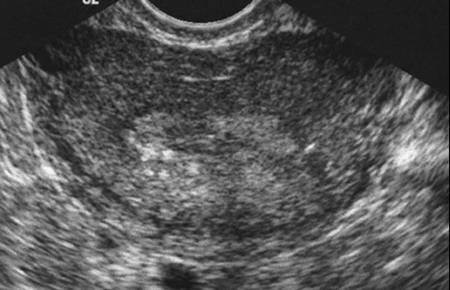

Adénomyose utérine (Cliché : Dr. C. TALMANT)